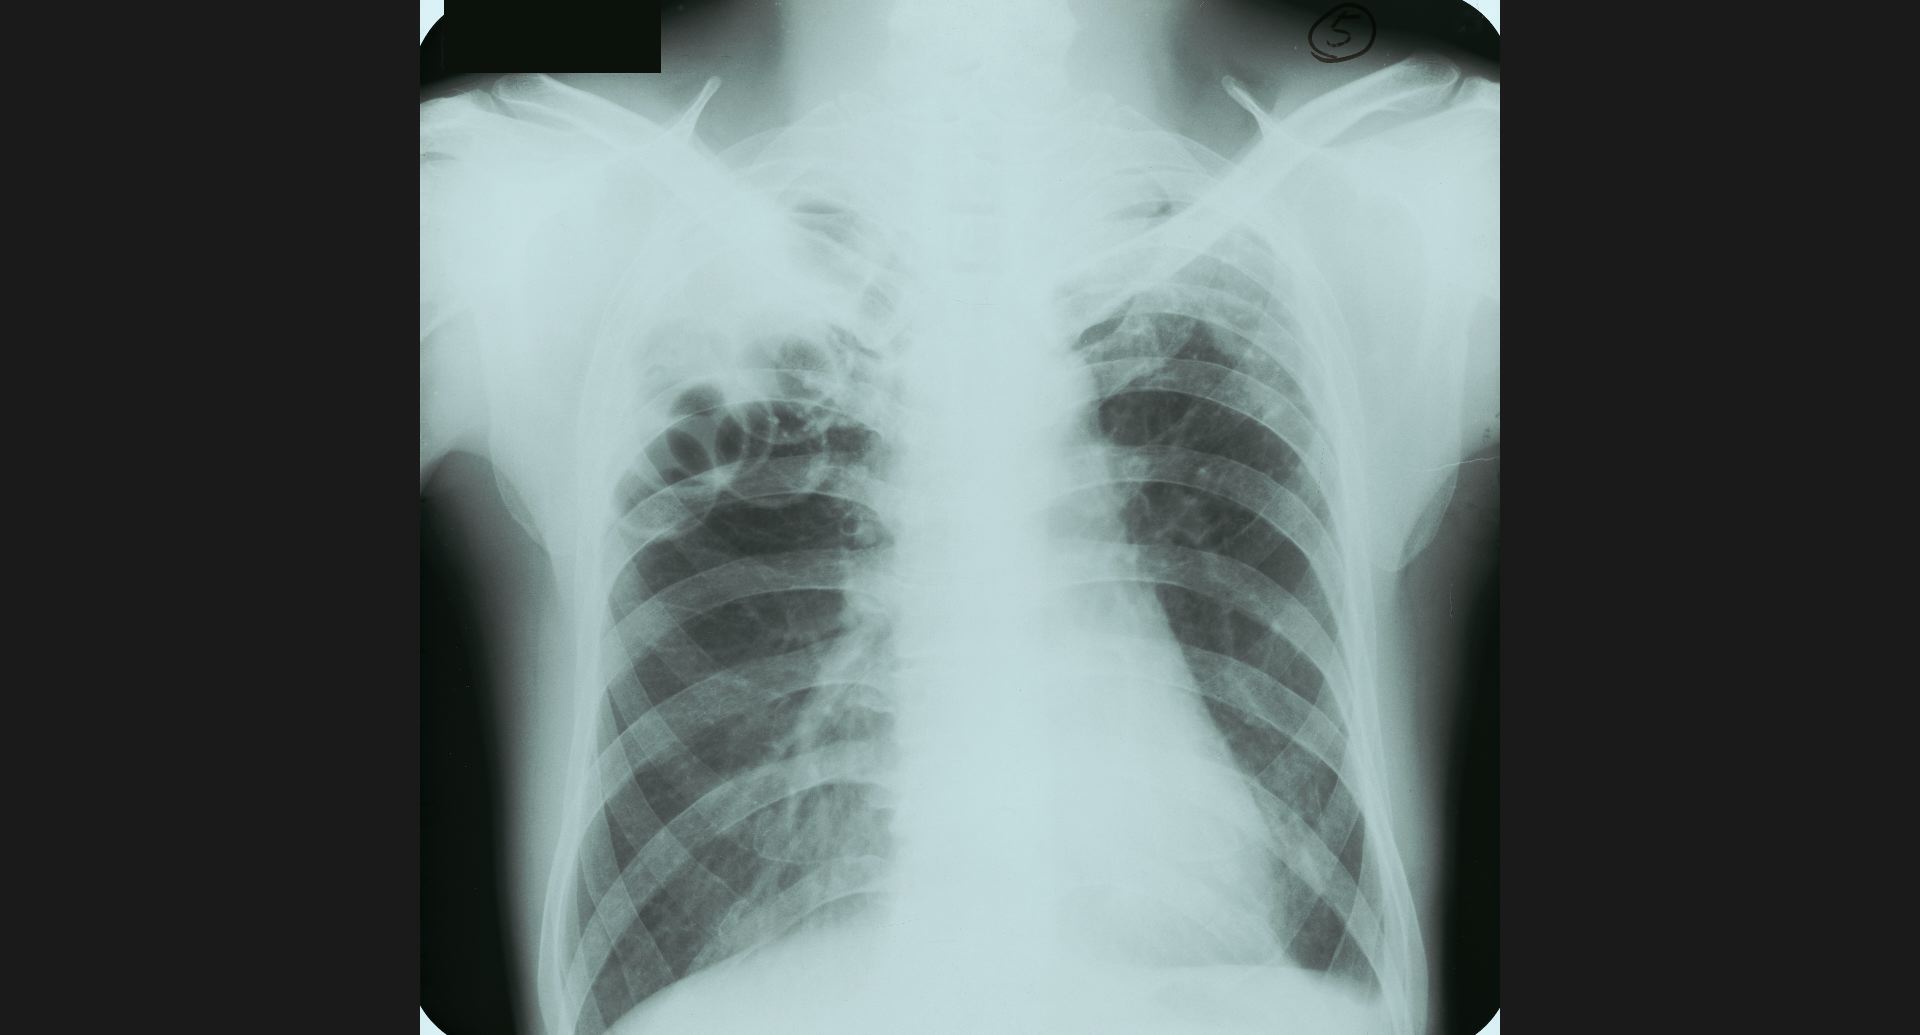

fig.5(93KB) :Post-plomboge chest

ピンポン玉、左肺上葉の細かい石灰巣。